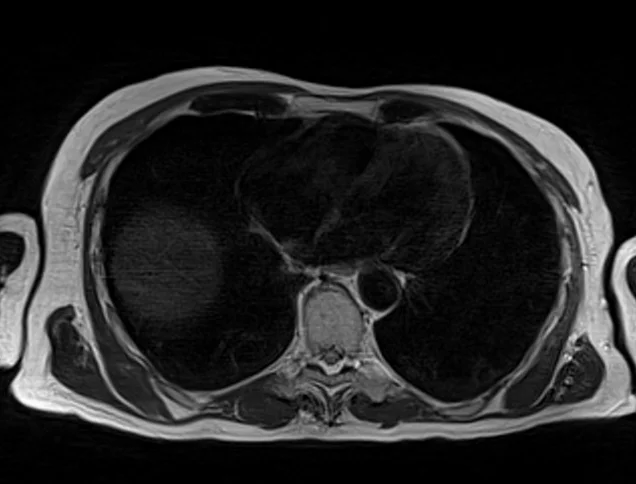

t2 1 - MRI